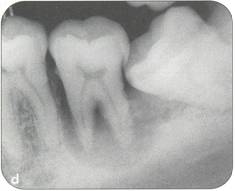

Fi 545e45f g 5-1d Preoperative periapical radiograph. |

Fi 545e45f g 5-8i Radiographic evaluation of the donor tooth. Several angulations should be used to determine the likely fit of the donor tooth into the recipient site. If the first premolar is double-rooted, consider using the second premolar as a donor tooth. |